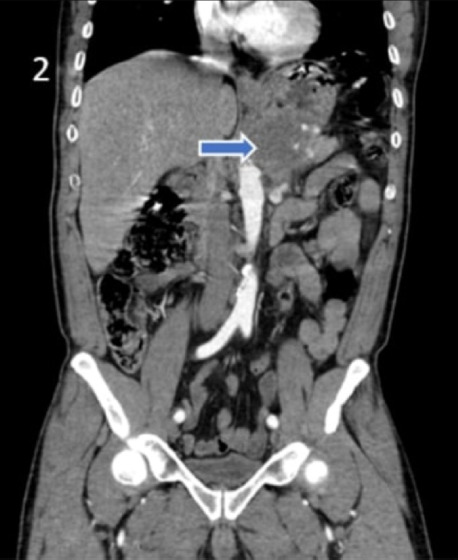

Pancreatic carcinosarcoma is one of the rare malignant tumors of the pancreas. Although they are aggressive, they can be detected with local or distant organ metastases when detected. In this article, the surgical procedure applied to pancreatic trophoblastic carcinosarcoma, which showed local invasion in a patient who applied to the emergency department of our hospital with the complaint of bloody vomiting and was operated with a preliminary diagnosis of gastric hemorrhage, the pathology result and the aggressive progression of the disease in a short time were presented. A literature review was conducted for pancreatic trophoblastic carcinosarcoma, which is a rare case, and the findings were presented.